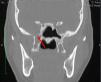

We report the surgical management of a spontaneous and recurrent nasal fistula using a temporoparietal fascial flap for definitive treatment after several failed attempts to close the fistula by conventional approaches. Two formalin-fixed cadaveric human heads were also dissected to study the anatomy and surgical technique involved in the design of the temporoparietal fascial flap.